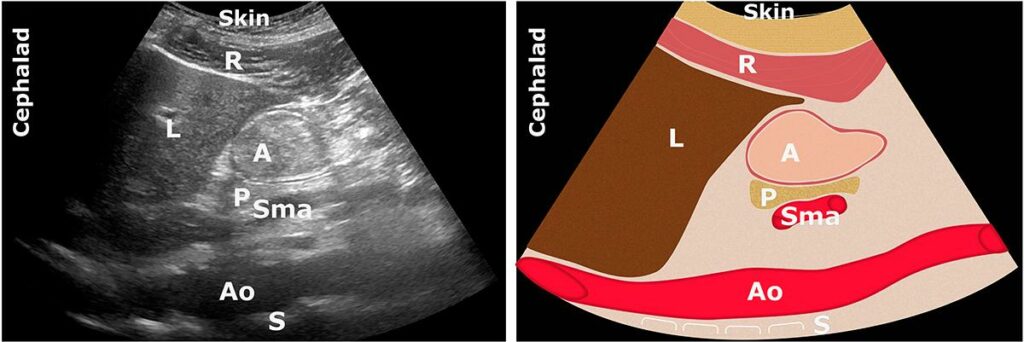

GEÇ DÖNEM KATI İÇERİK

A: Antrum; Ao: Aort; C: Kolon; L: Karaciğer; P: Pankreas; Sma: Süperior

mezenterik arter

Heterojen, partikül içerikleri (genellikle katı bir yemekten 1-2 saat sonra).